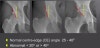

② Acetabular dysplasia, FA impingement 등의 평가에 유용

Hip dysplasia

Centre-edge(CE) Angle

Acetabular index

Proximal femur morphology

② 어린이와 청소년의 경우에는 골간단(metaphysis)이 모두 골단(epiphysis)에 덮여 있는지 확인합니다.

③ SCFE(Slipped capital femoral epiphysis)에서는 대퇴골 몸통 끝의 중심이 뼈끝 중심에서 전방으로 이동되어 있는 것을 알 수 있습니다.